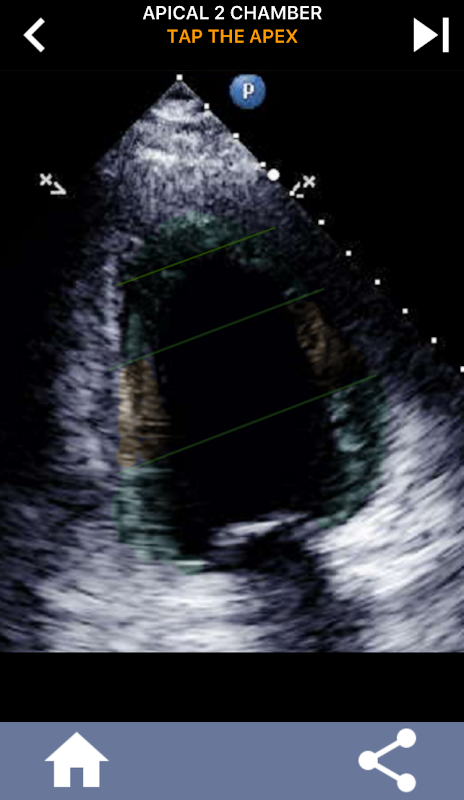

AHA دل کے حصوں کو سیکھنے کے لئے کوئز پر مبنی بصری نقطہ نظر: ایکو کارڈیوگرافی۔

AHA (امریکن ہارٹ ایسوسی ایشن) کے دل کے حصوں کو سمجھنا کارڈیک سونوگرافر کے لیے انتہائی اہمیت کا حامل ہے تاکہ وہ رپورٹ لکھنے والے ماہر امراض قلب کے ساتھ مؤثر طریقے سے بات چیت کر سکے۔ مخصوص جسمانی خطوں اور ان کے متعلقہ حصوں کو جان کر، سونوگرافر کسی بھی غیر معمولی باتوں یا نتائج کو درست طریقے سے بیان اور بات چیت کرسکتا ہے، دونوں پیشہ ور افراد کے درمیان واضح اور جامع مواصلت کو یقینی بناتا ہے۔

یہ تفہیم خاص طور پر اس وقت اہم ہو جاتی ہے جب ماہر امراض قلب کسی مسئلے کے صحیح محل وقوع کا پتہ لگانے کی کوشش کرتا ہے یا جب کال پر ڈاکٹر کسی مخصوص علاقے میں کسی مسئلے کی نشاندہی کرتا ہے، سونوگرافر کو متعلقہ طبقہ کو درست طریقے سے ظاہر کرنے کا اشارہ کرتا ہے، جیسے کہ درمیانی کمتر دیوار۔ اس طرح، AHA دل کے حصوں کی ایک جامع گرفت کا حامل ہونا ضروری مہارت کا مجموعہ ہے۔

یہ ایپ اصل ایکو امیجز کا استعمال کرتے ہوئے آپ کے علم کی جانچ کرے گی، جو مجھے اکثر پڑھانے کا بہترین طریقہ معلوم ہوتا ہے۔